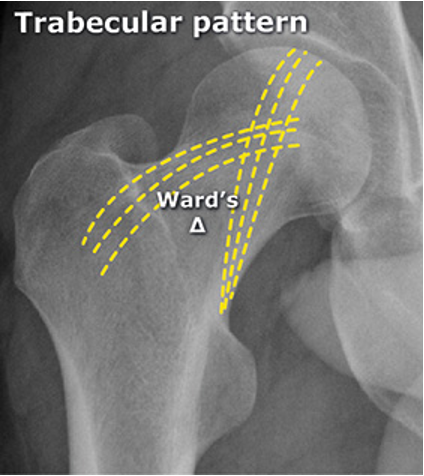

טרבקולות | Trabeculae

קורות עצם דקות המסודרות לפי קווי העומס

עקרונות חשובים:

- הסידור אינו אקראי - מותאם לכוחות הפועלים

- מתפתח ומשתנה עם הגיל והעומסים

- מעביר עומסים ביעילות מהמפרק לגוף העצם

דוגמה: ראש וצוואר הפמור

כוחות פועלים:

- באזור העליון: מתיחה (Tensile Forces)

- באזור התחתון: דחיסה (Compressive Forces)

התאמת הטרבקולות:

- טרבקולות מתיחה - מסודרות לאורך האזור העליון

- טרבקולות דחיסה - מסודרות לאורך האזור התחתון

- אזור חולשה (Ward’s Triangle) - בין שתי המערכות

חשיבות קלינית: שברי צוואר הפמור מתחילים תמיד באזור המתיחה (עליון-צידי)